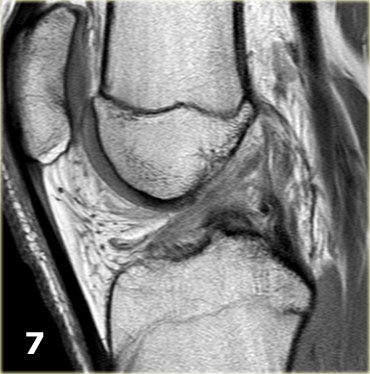

Rách kiểu quai xách (Bucket handle tear)

Trước tiên hãy quan sát các hình ảnh bên trái.

Chúng ta bắt đầu với lát cắt ở giữa của khảo sát.

Lưu ý thân sụn chêm bên có kích thước nhỏ với hình dạng bất thường (mũi tên xanh).

Phần bờ trong bị khuyết được nhìn thấy ngay phía ngoài dây chằng chéo trước (mũi tên đỏ). - Phần sụn chêm bị rách di lệch vào trong, tức là phần quai xách, có thể được theo dõi theo hướng ra sau trong hố gian lồi cầu.

- Tiếp tục.

- Đây là điểm nối giữa phần quai xách và sừng sau.

Rách kiểu quai xách là loại rách dọc theo chiều đứng có kèm di lệch.

Mảnh bờ trong bị di lệch có hình dạng giống như quai của một chiếc xô.

Phần ngoại vi còn lại của sụn chêm, phần lớn hơn, có hình dạng giống như thân chiếc xô.

Loại rách này chiếm khoảng 10% trong tổng số các trường hợp rách sụn chêm.

Dấu hiệu PCL đôi

Dấu hiệu dây chằng chéo sau (PCL) đôi là một dải giảm tín hiệu nằm song song và ở phía trước-dưới so với PCL trên ảnh MRI mặt phẳng đứng dọc.

Đây là dấu hiệu có độ đặc hiệu cao trong chẩn đoán rách sụn chêm kiểu quai xô (3).